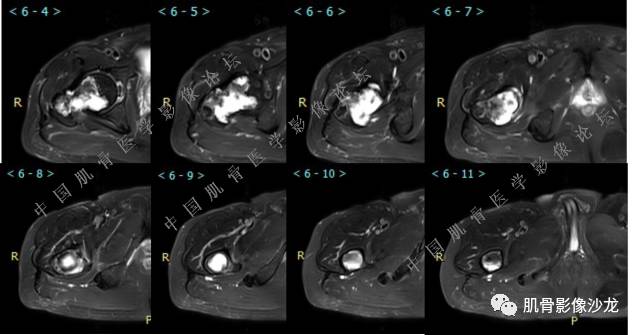

主诉:右大腿疼痛、活动受限20天

现病史:患者于20天前无明显诱因出现右下肢疼痛,活动受限,疼痛呈阵发性,活动后加重。自行口服止痛药芬必得,效果不佳,至当地医院治疗,检查发现右侧股骨近端病变。遂来诊

葛英霖 20:30 原发或继发动脉瘤样骨囊肿,继发于巨细胞瘤,软骨母,纤维组织细胞瘤,骨母等等

向以四 20:30 软骨母合并ABC,

医影在线 20:30 软骨母,/继发ABC

飞鹰行动 20:31 T2信号高,有软骨成分

Echo 20:32 T2确实有一块区域很亮 ,并有野液平

飞鹰行动 20:33 有侵袭性

飞鹰行动 20:35 骨皮质破坏,周围骨质异常信号

葛英霖 20:36 这不是良性病变

葛英霖 20:36 中间型可能性极大

葛英霖 20:37 明显侵蚀骨内膜啊,硬化边也不完整 (细箭头所示)

葛英霖 20:43 提不提也很明显继发了abc

葛英霖 20:44 是

葛英霖 20:46 明显的多囊状改变,液液平面